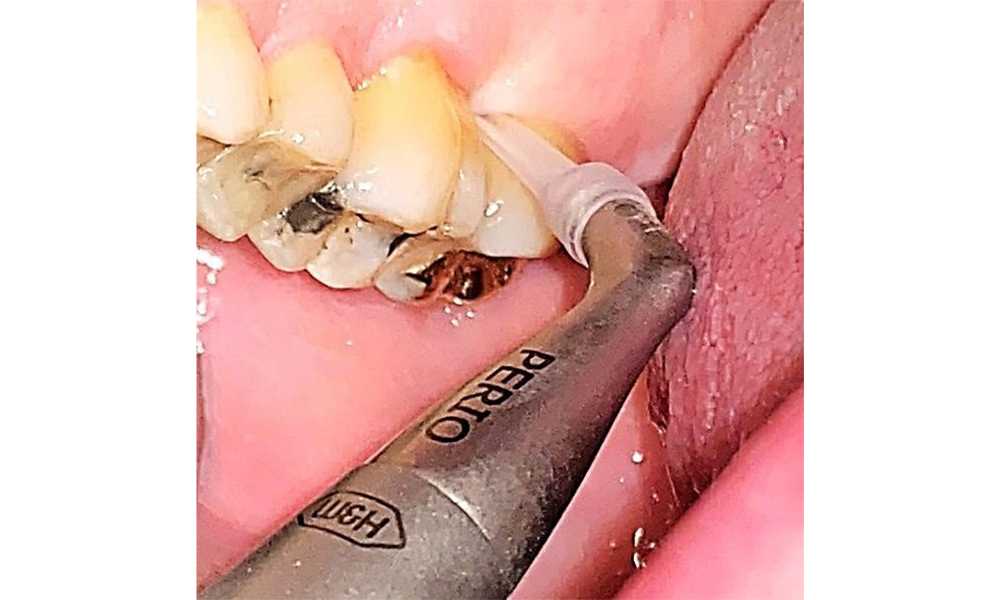

There are no limitations regarding the choice of instrumentation methods. Regular supragingival and subgingival instrumentation is essential to prevent disease progression due to the pre-existing periodontitis and high risk of recurrence. There are no limitations placed on the selection of instruments for mechanical biofilm removal from a general medical perspective, and removal should be performed as needed. Hard and mineralized plaque, such as calculus and concretions, should be removed using manual instruments or sonic/ultrasonic scalers (Fig. 9) (8, 9).

Use an ultrasonic tip to remove hard, mineralized plaque (Proxeo Ultra scaler with the Perio tip, W&H, shown here). © Dr R. Krapf

Fig. 9: Use an ultrasonic tip to remove hard, mineralized plaque (Proxeo Ultra scaler with the Perio tip, W&H, shown here). © Dr R. Krapf